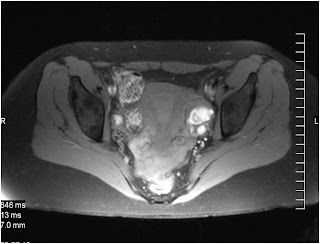

caso 11-11-02

mujer de 43 años con tumoración anexial izquierda detectada en una ecografía abdominal (MAF)